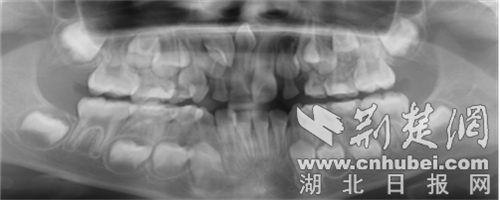

医学检查:最准确的方式是做口腔X光片或口腔CT,尤其是埋伏在颌骨内的多生牙,只有通过影像才能确定其位置、数量和形态,为治疗提供依据。

它的“存在感”可强可弱:有的多生牙会像正常牙齿一样萌出,肉眼就能看到;有的则一直埋伏在颌骨内,只有拍X光片(如口腔CT)时才会被发现。从形态上看,它也很“任性”——可能是正常的牙齿形状,也可能是畸形的小颗粒,颜色、大小都与正常牙齿有明显差异。

需要注意的是,拔除多生牙需由专业口腔医生评估,尤其是埋伏较深的多生牙,需通过CT制定精准的手术方案,降低风险。